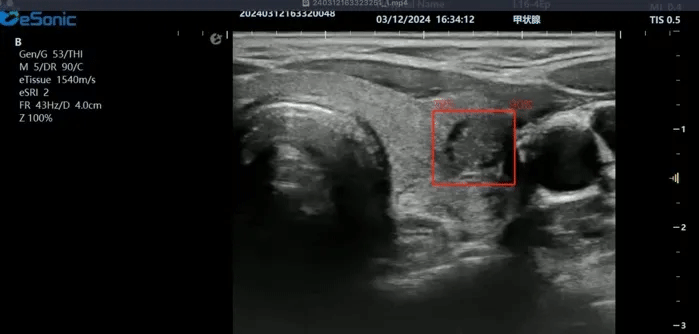

百乐博平台医疗(ESI)表示,其最新的人工智能功能可以帮助到医疗机构的工作效率,功能包括,实时、动态、快速自动识别病灶,良恶性病灶概率预测,甲状腺结节和乳腺的二维灰阶动态自动实时检测需求,提供多个结节动态检测轮廓框。实时获取多幅具备临床特征(大小、属性等)的结节切面,同时提供当前切面所示结节的结节大小、属性特征、TI-RADS 分级。

对于甲状腺结节相关的自动检测功能,甲状腺结节病灶检出率≥95%,良恶性分类灵敏度≥90%、良恶性分类特异度≥85%。